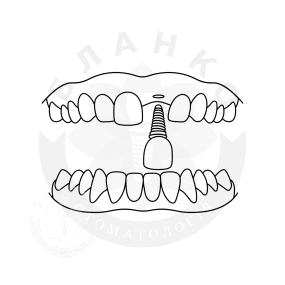

Зубна імплантація — це сучасне та надійне рішення для відновлення втрачених зубів. У стоматологічній клініці Бланко ми пропонуємо імплантацію зубів «під ключ», що означає повний комплекс послуг — від діагностики до встановлення коронки, без прихованих платежів та несподіваних витрат.